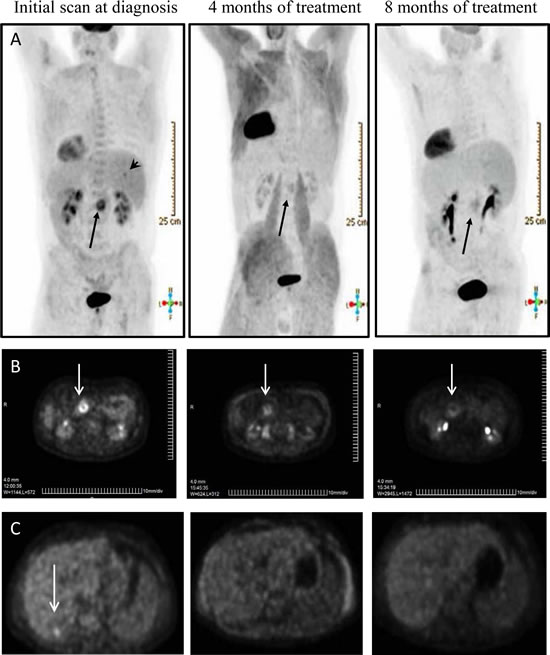

Compound C4 is a small molecule chloropyramine hydrochloride known as a competitive reversible H1-receptor antagonist, widely used in Eastern Europe and available over the counter. Figure 7A shows CT scan image of a patient with stage IV pancreatic cancer who personally elected to take daily oral chloropyramine hydrochloride, in parallel with the standard course of gemcitabine chemotherapy. Figure 7B shows significant clinical response of primary tumor over an eight month period of dual treatment. Importantly, liver metastasis seen on initial CT and PET scan, has shown a complete clinical response over an eight month period (Figure 7C).

Figure 7: Prolonged regression of stage IV pancreatic cancer (primary tumor and liver metastasis) treated with C4 in combination with gemcitabine. A. Axial PET scans show liver metastasis (arrowhead) on initial scan, undetectable 4 and 8 months after treatment with C4 and chemotherapy. Primary tumor (arrow) shows marked response to treatment with minimal PET activity. Scans oriented to view patient from behind (liver on right side). B. PET scans show sequential response of advanced pancreatic cancer after treatment with C4 and chemotherapy. The primary tumor in the pancreas (arrow) shows sustained regression over 8 months of treatment. C. PET scan at diagnosis of Stage IV pancreatic adenocarcinoma demonstrates liver metastasis (arrow). Scans demonstrated a complete clinical response after 4 and 8 months of treatment with C4 and chemotherapy.